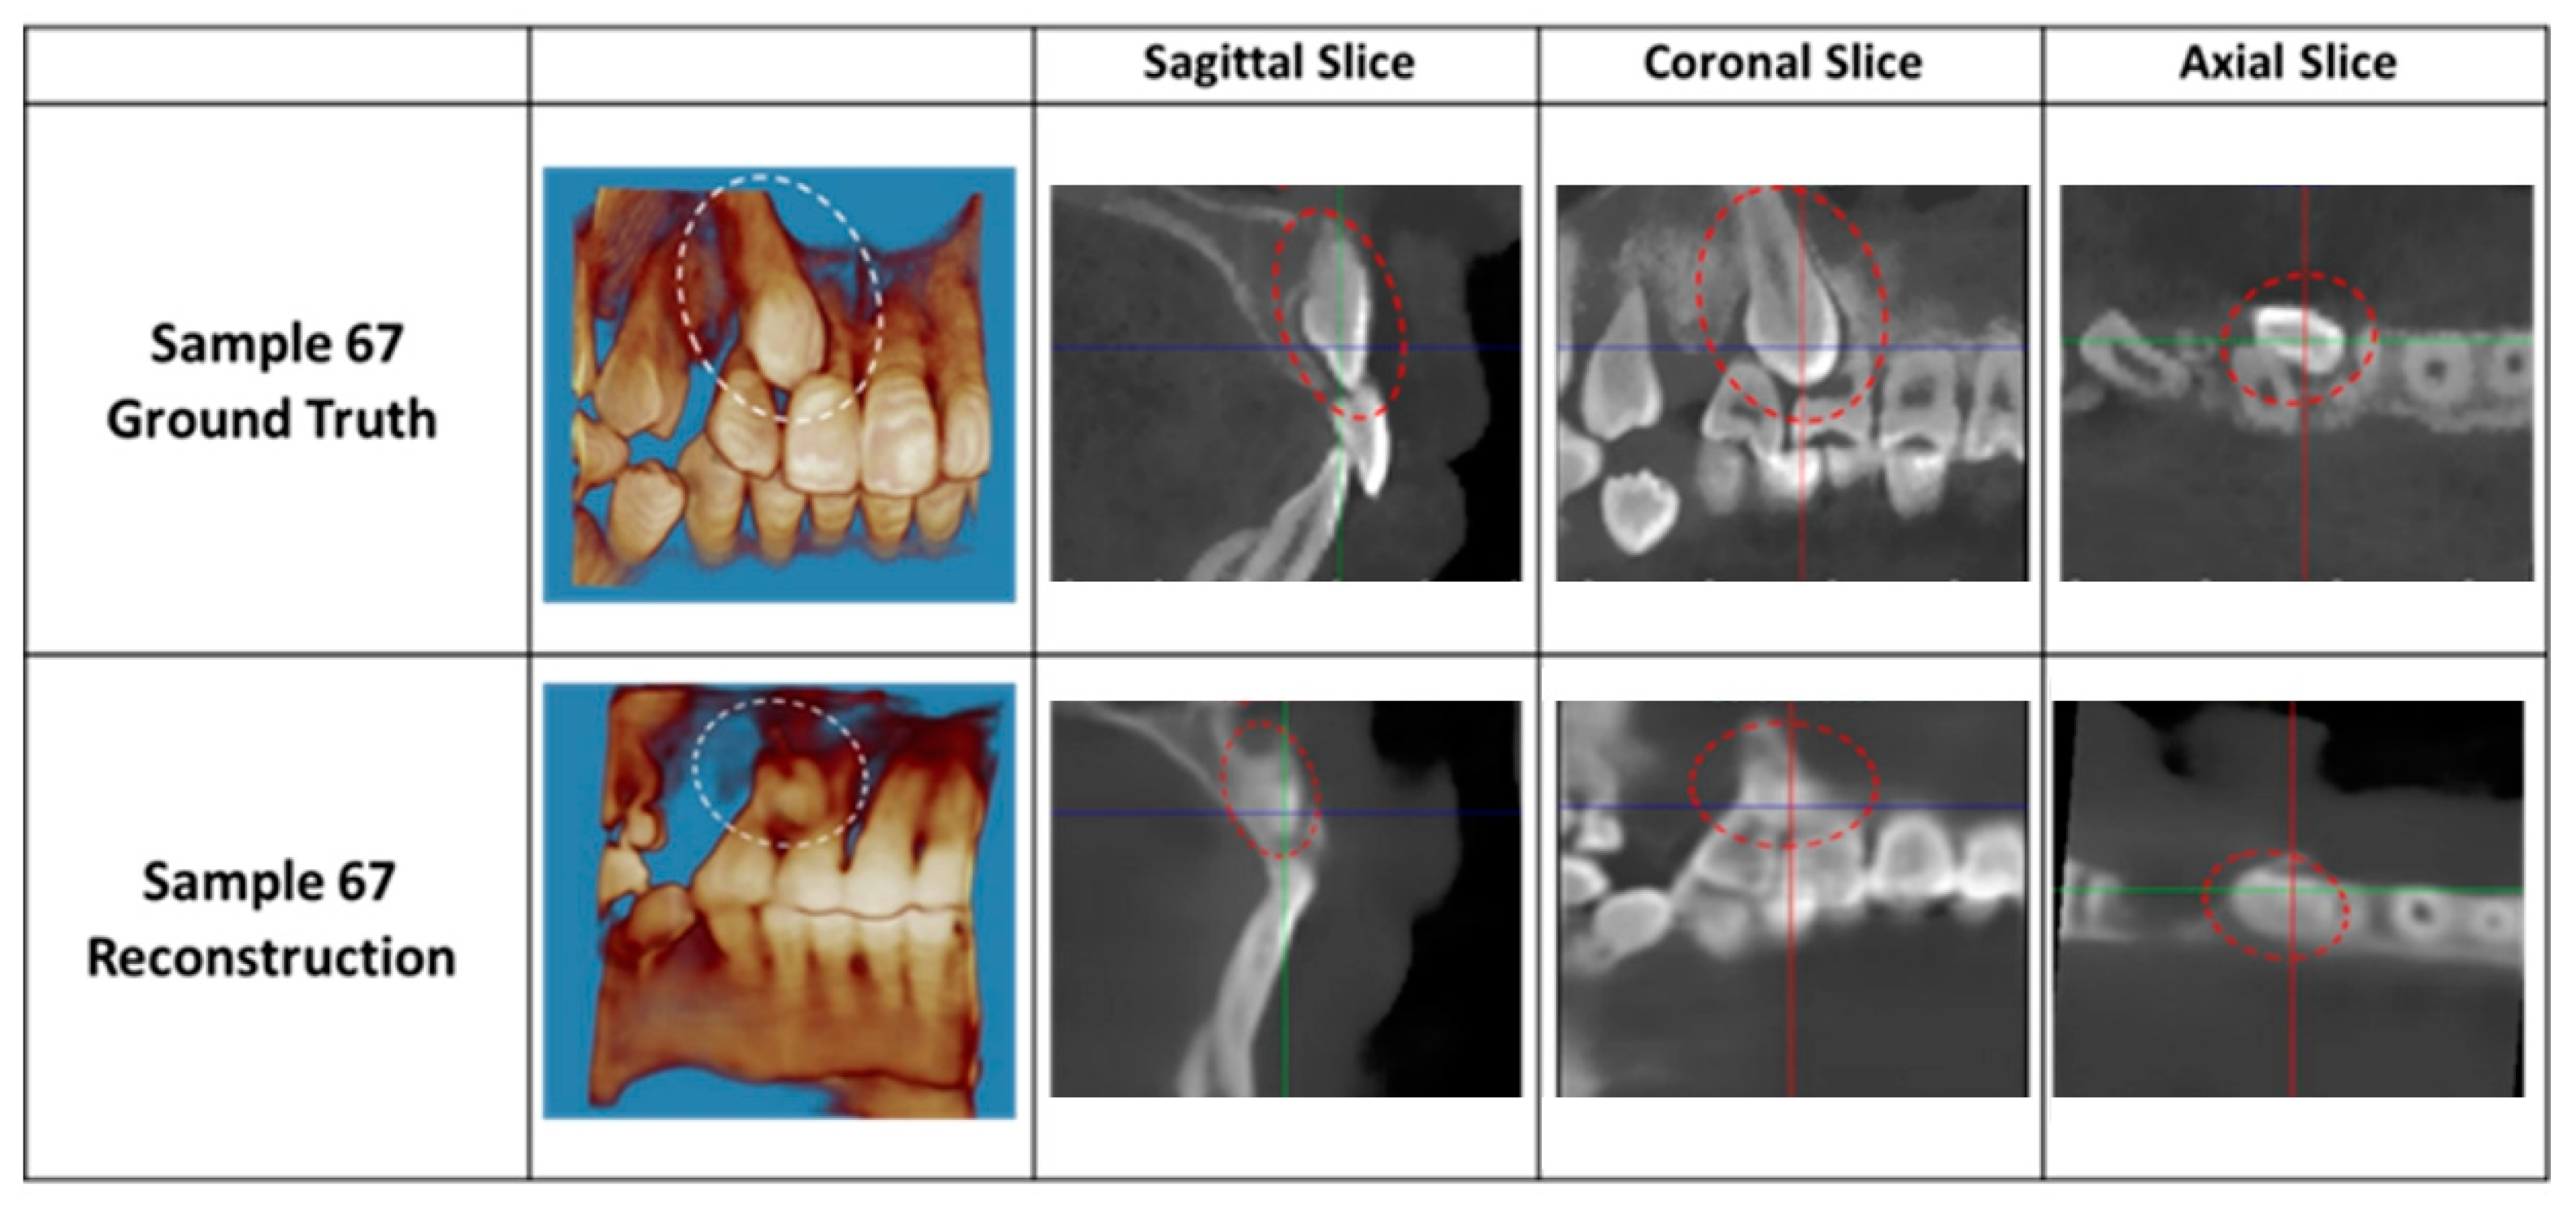

3. Results